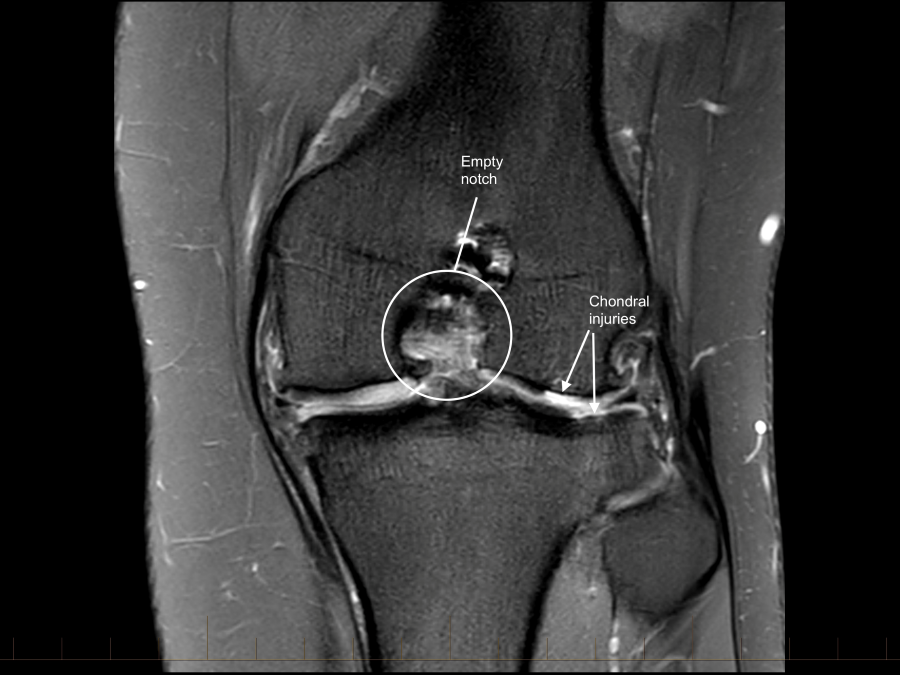

The ACL graft is ruptured with a loss of the normal ACL contour and signal. There is a focal are of full-thickness cartilage loss on the posterior, weight-bearing portion of the lateral femoral condyle. This measure approximately 15 x 10mm. There is also thinning and irregularity of the articular cartilage involving the posterior aspect of the lateral tibial plateau with a small area of full thickness cartilage loss and subchondral reactive change. These chondral changes were not present at the time of her first surgery. There appears to have been trimming of the mid and posterior thirds of both menisci. These meniscal remnants are small and irregular.